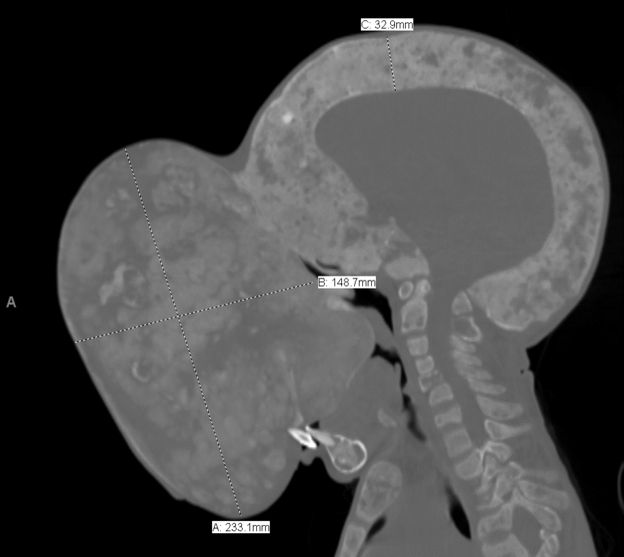

NUEVA YORK.- Un tumor del tamaño de una pelota de rubgy le cubre la cara desde hace más dos años y le obstruye el campo visual, las vías nasales y la boca.

Este adolescente cubano, oriundo de la provincia de Villa Clara, en el centro de la isla, tampoco puede ya caminar, porque el peso del quiste (más de 4,5 kilogramos), le impide mantener en equilibrio la cabeza y los médicos temen que, de seguir creciendo, pueda provocarle una fractura fatal de cuello.

“Es un caso atípico y lleno de riesgos, pero la operación es necesaria. Si el tumor sigue creciendo, puede terminar de obstruirle la boca, que es ahora la única vía de entrada de alimentos y aire para él. También el tumor, por su peso y tamaño, podría provocar una fractura de médula al nivel del cuello”, explica.